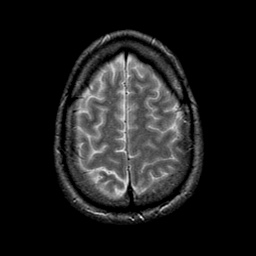

glioma overlay -- Slice #23

[Home][Help][Clinical] Slice 23